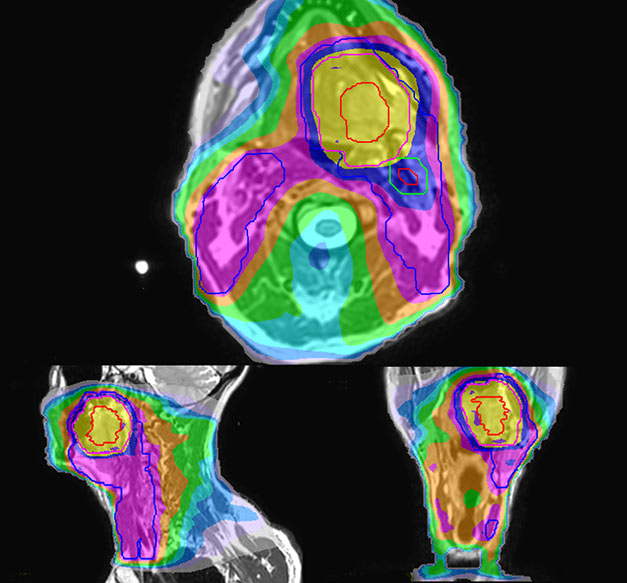

Epidermoid carcinoma of the left tongue base

The patient was diagnosed with an epidermoid carcinoma of the base of the left invading the amygdala lodge and the amygdaloglossal groove. Radiochemotherapy with curative aim was prescribed with a dose of 70 Gy for the tumor, 66 Gy on the suspicious nodes and 56 Gy on the elective drainage areas - in 33 fractions.

T2W 3D, 3D STIR and mDIXON MRI scans.

Comparison of CT simulation scan (left) and T2W 3D MRI (right)

MR-based target contouring on 3D T2W TSE in transversal, sagittal and coronal planes.

Personalized VMAT dose planned in Philips Pinnacle.